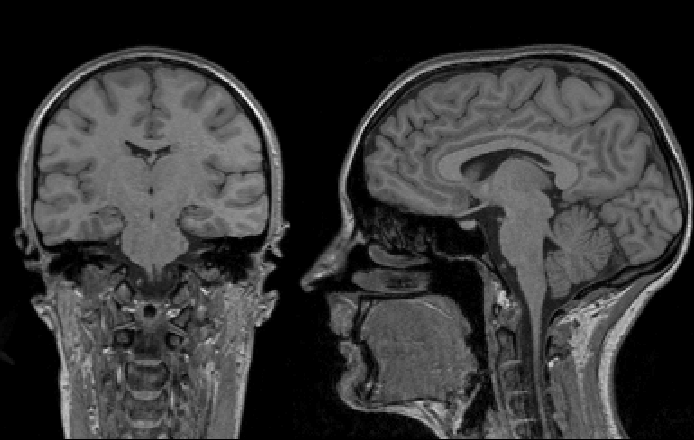

3 тесла ребенку

3 тесла ребенку 86 фото